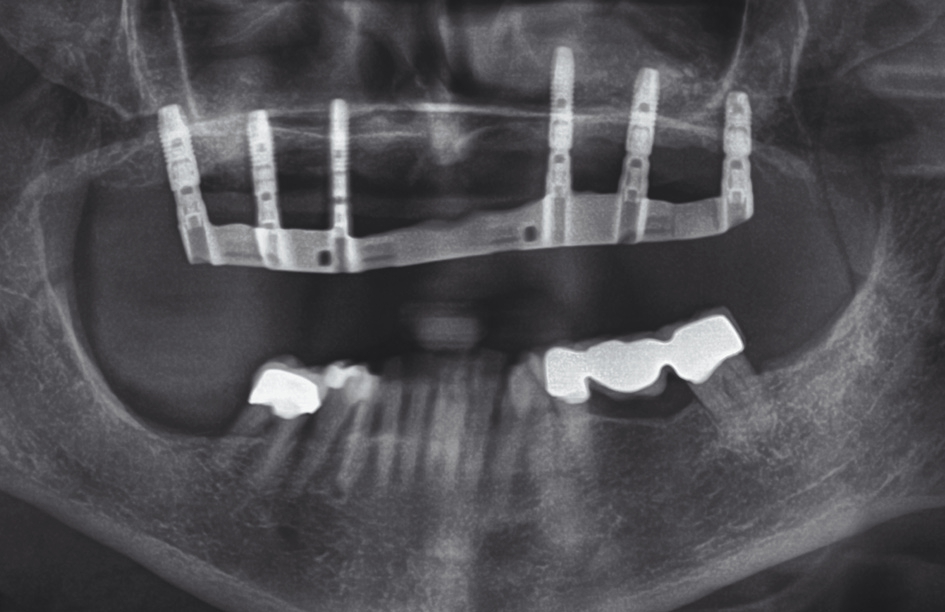

Vor dem zweiten OP-Eingriff nach 4 Monaten wurde im Labor eine Bohrschablone angefertigt. Zudem wurde ein DVT angefertigt, um im Sinne eines Backward planning die ideale Implantatposition planen zu können. Bei Eröffnung des augmentierten Kieferbereiches zeigte sich im augmentierten Bereich eine gute Regeneration und Revaskularisierung des Knochens (Abb. 14 bis 17). Sechs Implantate konnten somit in den augmentierten Bereich (Astratech EV®, DENTSPLY Sirona, Mannheim) mit ausreichender Länge und Durchmesser in Form einer gleichmäßigen Pfeilerverteilung in den Kieferknochen Inseriert werden (Abb. 18).

Die Passung der definitiven Restauration wurde im Mund des Patienten mithilfe des Sheffield-Testes überprüft, mit dem die Passgenauigkeit einer primär verblockten Mesio-Struktur überprüft werden kann. Hierbei wird nach Aufsetzen der Mesio-Struktur jede einzelne Halteschraube separat angezogen, ohne die jeweils anderen zu aktivieren. Dies dient der exakten Überprüfung einer präzisen Passung, da bei ungenügender Passgenauigkeit bei Anziehen nur einer Schraube eine Kippung und Spaltbildung am Gerüst auftreten würde, welche röntgenologisch zu erkennen ist.

Nachdem die Passung und Ästhetik der fertigen Arbeit erneut von Behandler und Patientin überprüft worden waren, konnte die Arbeit definitiv eingesetzt werden (Abb. 26 und 27). Anschließend wurde die Patientin in den Gebrauch der Riegelvorrichtung eingewiesen sowie über die Mund- und Prothesenpflegemaßnahmen aufgeklärt (Abb. 28). Durch die Einbindung des Patienten in ein halbjährliches Recallprogramm kann in regelmäßigen Abständen der Sitz der Konstruktion und der periimplantäre Zustand überprüft werden.